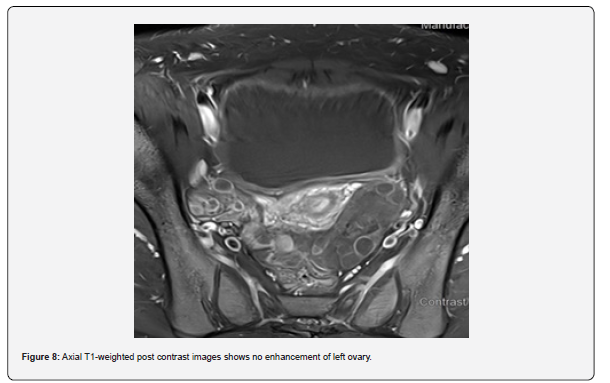

The patient is a 12-year-old girl who presented to emergency department with severe left-sided abdominal pain associated with persistent vomiting for the past two days. On physical examination left flank tenderness was noted with radiation to suprapubic area, there was no diarrhea or fever. Pelvic ultrasound with Doppler demonstrated bilaterally enlarged ovaries with small follicles with a markedly enlarged left ovary showing reduced vascularity and no evidence of identifiable ovarian cyst (Figures 1-4). Magnetic resonance imaging (MRI) demonstrated bilateral ovarian enlargement with multiple small follicles, assuming polycystic ovarian morphology. The left ovary was significantly enlarged, positioned posterior to the uterus and showed stromal edema with decreased post-contrast enhancement compared to contralateral side, findings consistent with ovarian torsion (Figures 5-10).

No definite ovarian cyst was identified on MRI. Mild free fluid was noted in the left adnexa. Patient underwent emergency laparoscopy and ovarian torsion was confirmed intraoperatively. Left ovary was found enlarged and torsed with two twists. A small ovarian cyst measuring approximately 2x2 cm was detected. Ovarian sparing laparoscopic detorsion of the left ovary was performed with cyst marsupialization. Patients were discharged on postoperative day 3 in stable condition. Follow-up visit in clinic after one week showed uneventful recovery. This case report highlights the importance of prompt diagnosis of ovarian torsion for timely surgical intervention even in absence of detectable cyst on imaging. aiming to preserve ovarian torsion and future fertility.